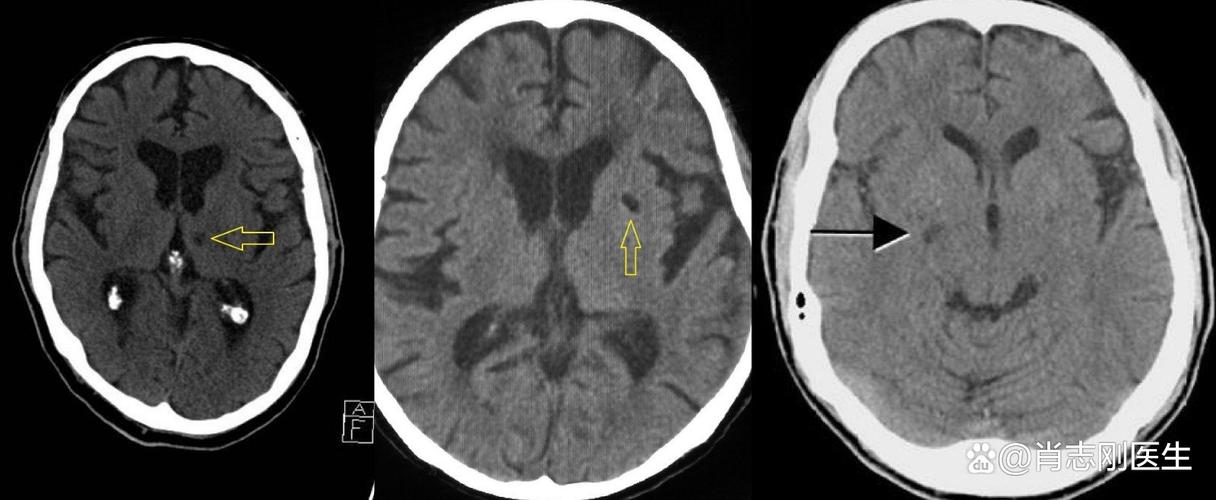

“脑内多发缺血、脑梗灶” 指的是:在大脑的多个区域,存在着一些因长期或急性脑部缺血而形成的、已经坏死的脑组织小斑点。

- 在脑部:当缺血持续足够长的时间(通常是几分钟),导致脑细胞因为缺氧而死亡,这个过程就叫做“脑梗死”(或脑梗塞),死亡的脑组织无法再生,会形成一个永久的、坏死的区域,在影像学上(CT或MRI)就表现为一个“梗灶”或“软化灶”。

- 在脑部:报告中的“多发”说明这种缺血性坏死不是孤立的,而是在大脑的不同部位出现了多个小梗灶,这通常意味着脑血管的病变是广泛性、弥漫性的,而不是单一某个血管出了问题。

- “缺血、梗灶” 这个描述通常指的是陈旧性的病灶,也就是说,这些小梗塞可能发生在数周、数月甚至数年前,它们是过去曾经发生过“小中风”或“无症状性脑缺血”留下的“疤痕”。